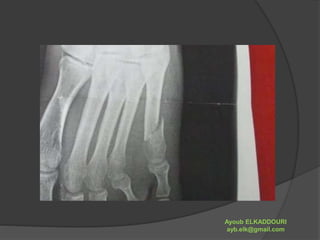

 Le pied contient 26 os en moyenne.

 Il est composé de 3 éléments principaux :

 le tarse, dont les os comprennent :

 le calcanéum, qui compose le talon,

 l'astragale sur laquelle s'appuient les os de la

jambe (tibia, fibula),

 les os cunéiformes,

 et le scaphoïde.

 le métatarse (composé de 5 os),

 les phalanges : os des orteils.